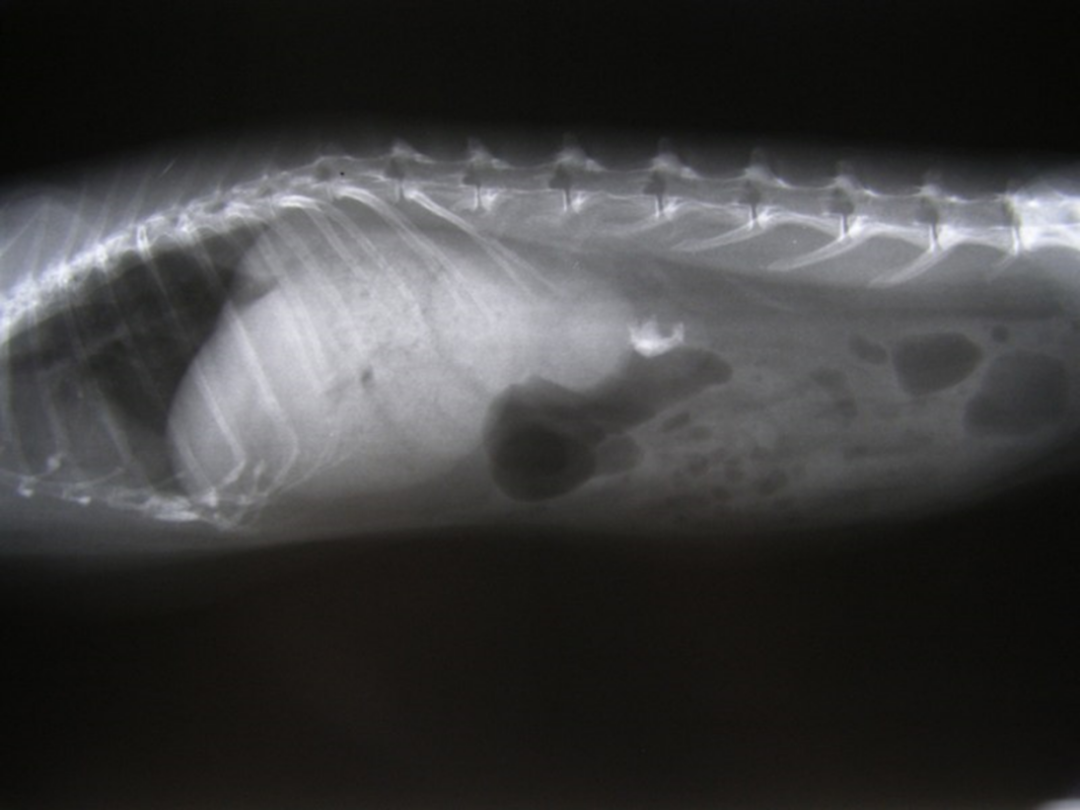

鸟类有很大的区别。这里提到的主要是跟麻醉相关的一些问题了。这里面就是它会容易出现这种低体温的倾向。不但是鸟类,小的小型哺乳动物和两爬也会。他们的残气量非常小,心率很高,代谢率也很高,容易出现捕捉性肌病。鸟的骨骼非常的薄和脆弱,很多鸟类体内里面是有气囊的。在鸟出现骨折的时候做手术,吸入麻醉的药物有可能会通过这个骨折断端泄露出来。羽毛对鸟类非常重要,它不但是帮助鸟类飞行的,也用来保温。在术前如果我们要给这个鸟去拔毛,可能造成它去没有办法保护自己,保护体温。

另外在鸟类上会有产蛋前出现的一些生理性的多骨性的骨增生。

动物怎么麻醉手术环境、对象和物种差异对异宠麻醉的影响【长文预警】_https://www.jmylbn.com_新闻资讯_第32张